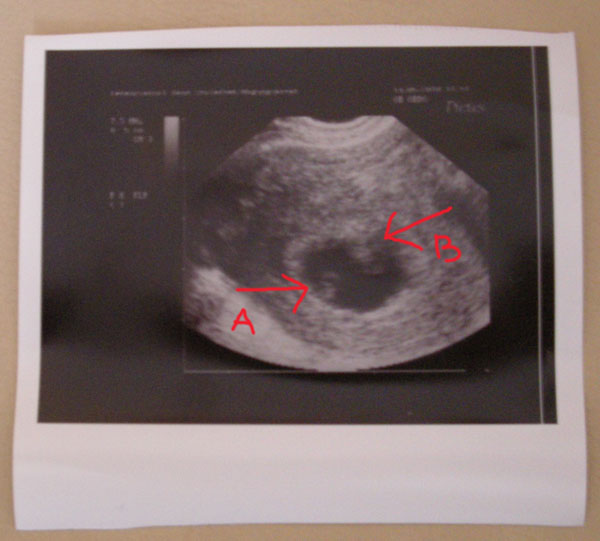

Kép

sztárfotónk 3in1